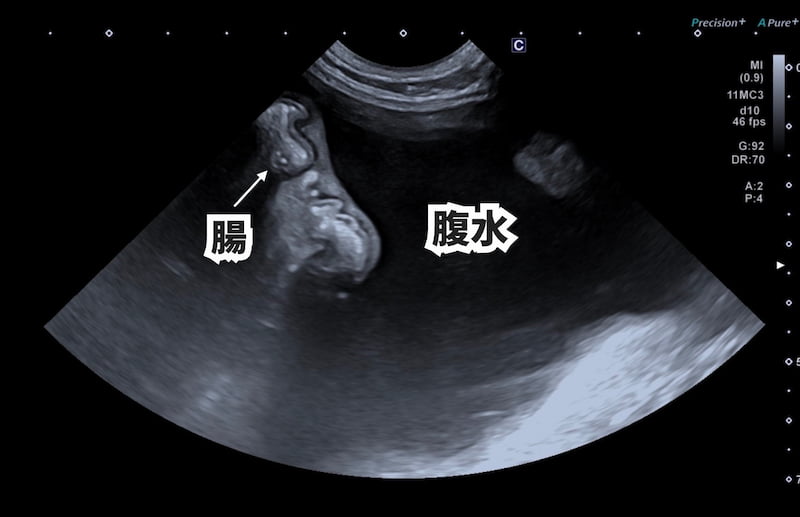

一般内科(総合診療科)

猫伝染性腹膜炎(FIP)について|モルヌピラビルで寛解した症例